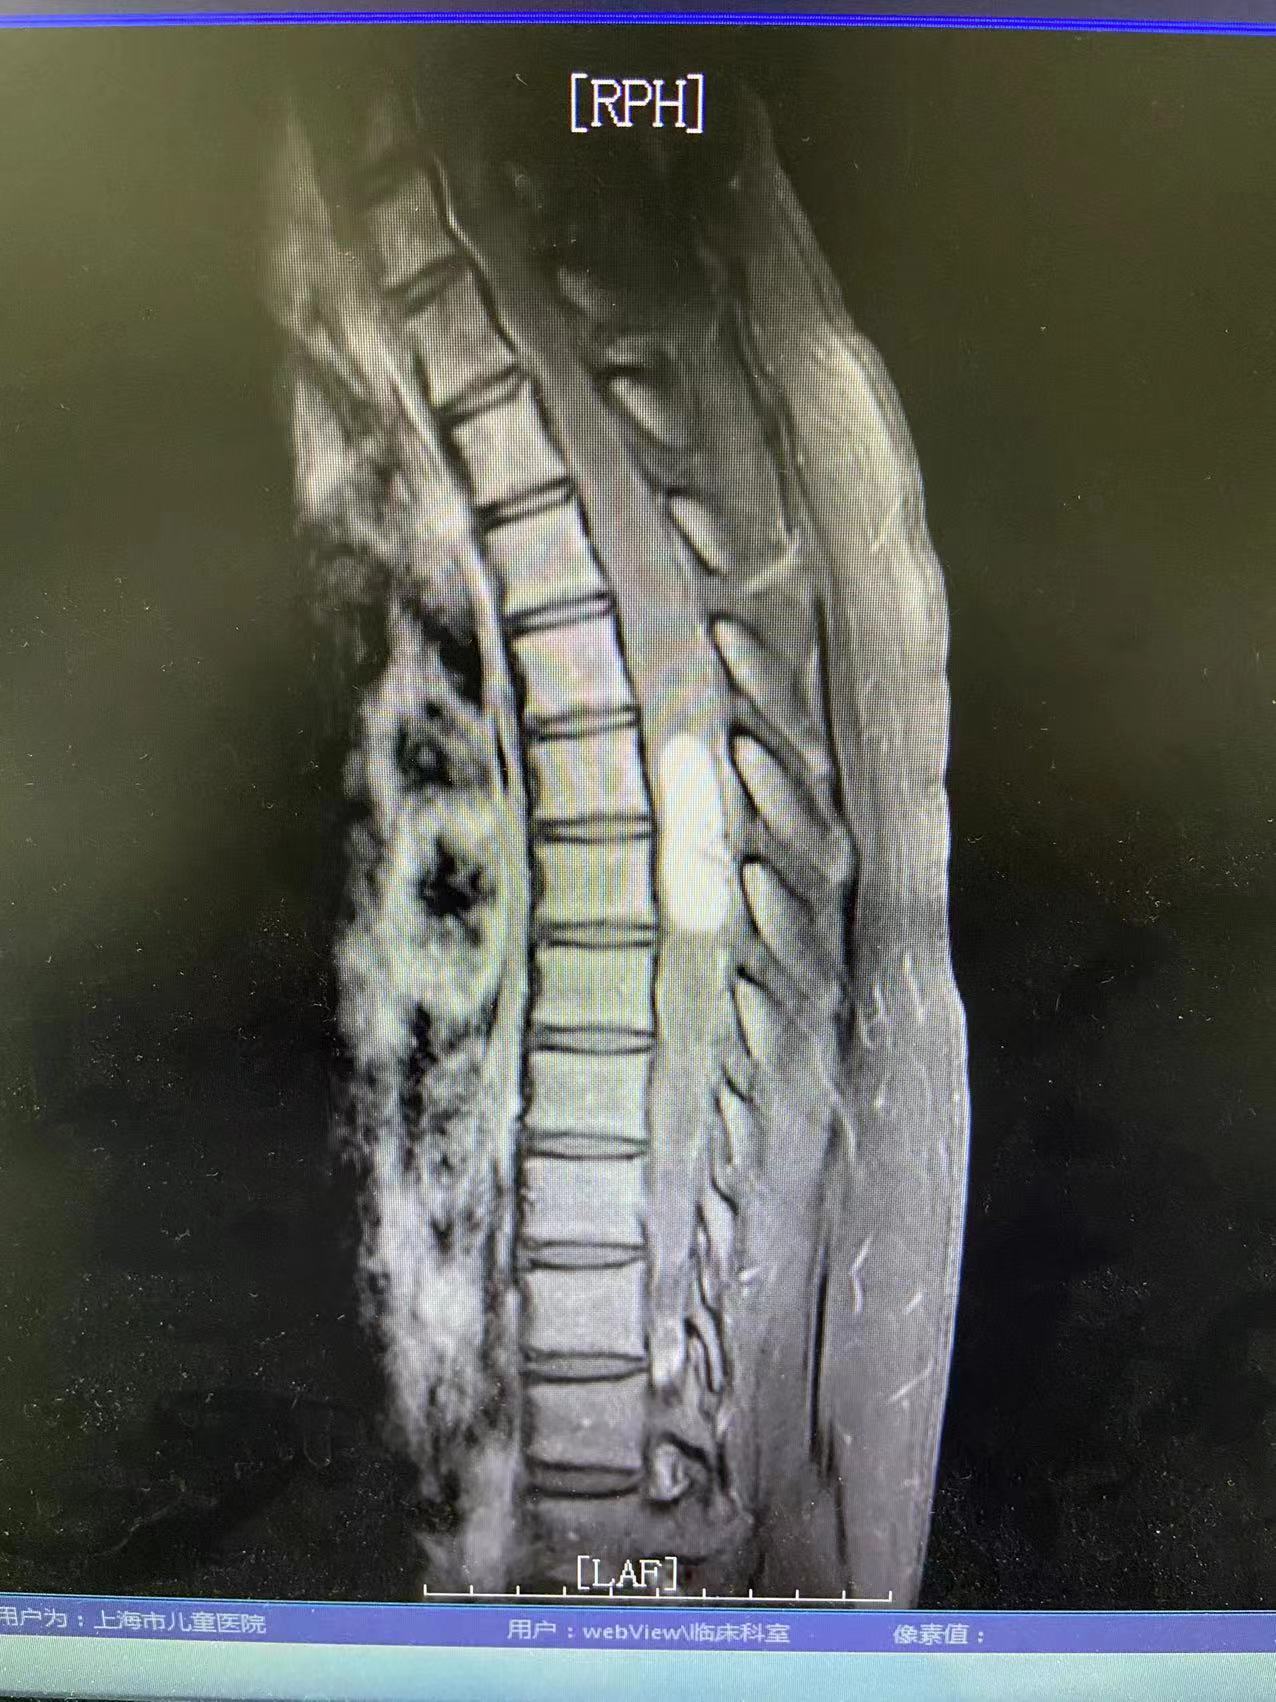

经详细检查诊断,清清所患的疾病是脊髓血管母细胞瘤,是一种由脑神经和脊髓神经产生的高度血管分化的良性肿瘤。虽说是良性,但随着病情的发展,肿瘤越长越大,会压迫脊髓神经,继而造成相应的功能受损。而且清清的肿瘤位于上胸段,如果不尽快手术切除,持续增大的肿瘤会引起严重的并发症,如肿瘤平面以下肢体瘫痪、尿失禁等。因此,为了避免病情的恶化,需要尽快开展手术,而在切除肿瘤的同时保证脊髓功能的完好,又为这台手术的开展增加了很大难度。

为此,神经外科医疗团队采用国内外最先进的技术和方法,制定出一套详尽的治疗方案;并在术中运用持续同步的感觉诱发电位(SEPs)和动作诱发电位(MEPs)的监测,加上专职的神经电生理监护师保驾护航,最终手术顺利完成,完整切除肿瘤,清清的病情得到了有效控制,且术后身体运动功能良好,没有出现任何手术相关并发症。